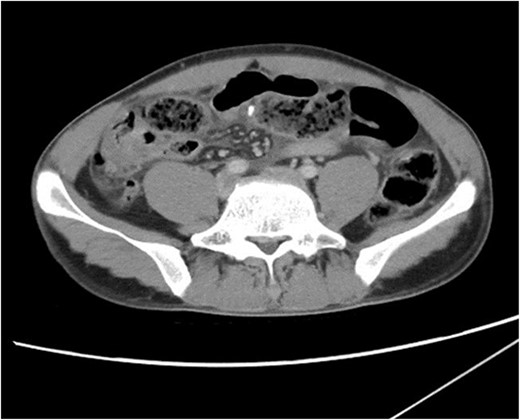

CT scan of abdomen and pelvis. A radiopaque object is seen extruding from a thickened small bowel loop with associated free peritoneal fluid, concerning for foreign body perforation of small bowel.

Following imaging and discussion with the patient, we proceeded to emergency laparotomy. On evaluating the small bowel, an enterotomy was noted in the mid jejunum due to a protruding fractured piece of frog bone (see Figs 3 and 4). There was associated localised peritonitis, but no gross peritoneal contamination. A sample was taken for culture and sensitivity, but no growth was ultimately seen. A decision was made to proceed with a primary repair of the enterotomy as the surrounding small bowel tissue was healthy, and this was performed in two-layers with interrupted 4–0 PDS. An extensive abdominal washout was performed prior to closure. The patient made an uneventful post-operative recovery and was discharged home well on post-operative Day 7.